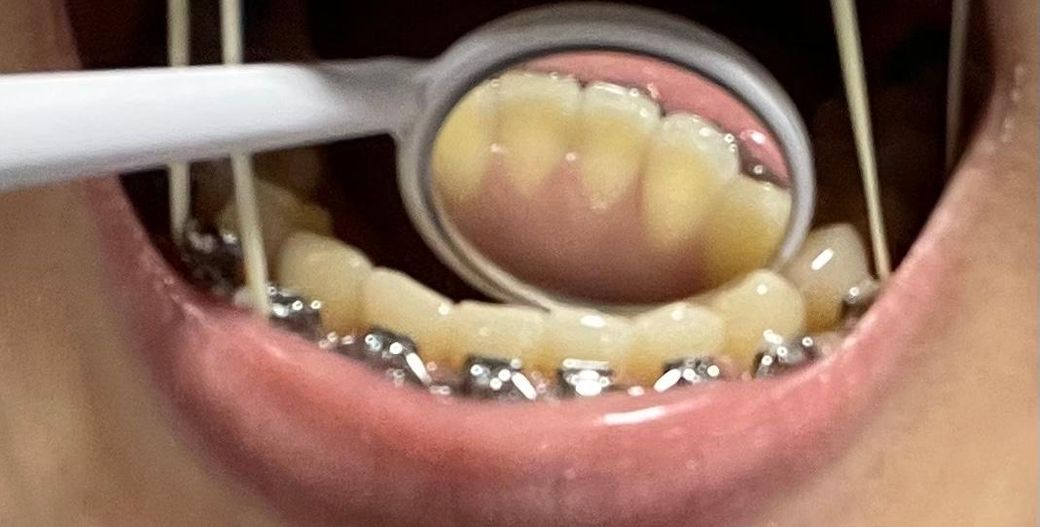

그리고 2,3번째 사진은 현재인데, 평소에 신경 안쓰고 살다가 우연히 보게 됐는데 아랫니 치아 안쪽 잇몸이 너무 v자로 파진 느낌이 드는데 원래 그런건가요?

• 3번 째 사진

방사선 사진 상에서 치근 길이 엄청 짧거나 이상있어 보이지는 않으며 구내 사진 상에서도 큰 이상은 없어보입니다. 교정 치료 중에는 치아 이동에 따른 치근 흡수가 발생할 수 있으며 교장 합병증 중 하나입니다.

지금 첨부 주신 사진상에서는 큰 이상은 없어보입니다. 너무 걱정하지는 않으셔도 될 것 같으며 자세한 것들은 사진 자료가 있는 교정 치과에서 꼭 이야기 나눠보시기를 바랍니다.